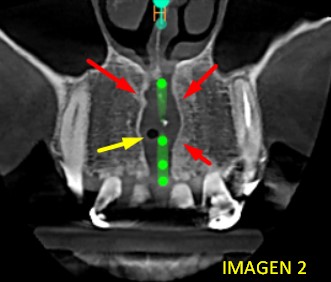

​Al realizar el barrido tomográfico, pudimos observar un defecto óseo que se extiende desde el piso de fosas nasales comprometiendo el hueso alveolar de la zona. (VER IMAGEN 2)  Corte coronal, se observa ensanchamiento del canal nasopaltino (flechas rojas), y una cavidad de aire (flecha amarilla).